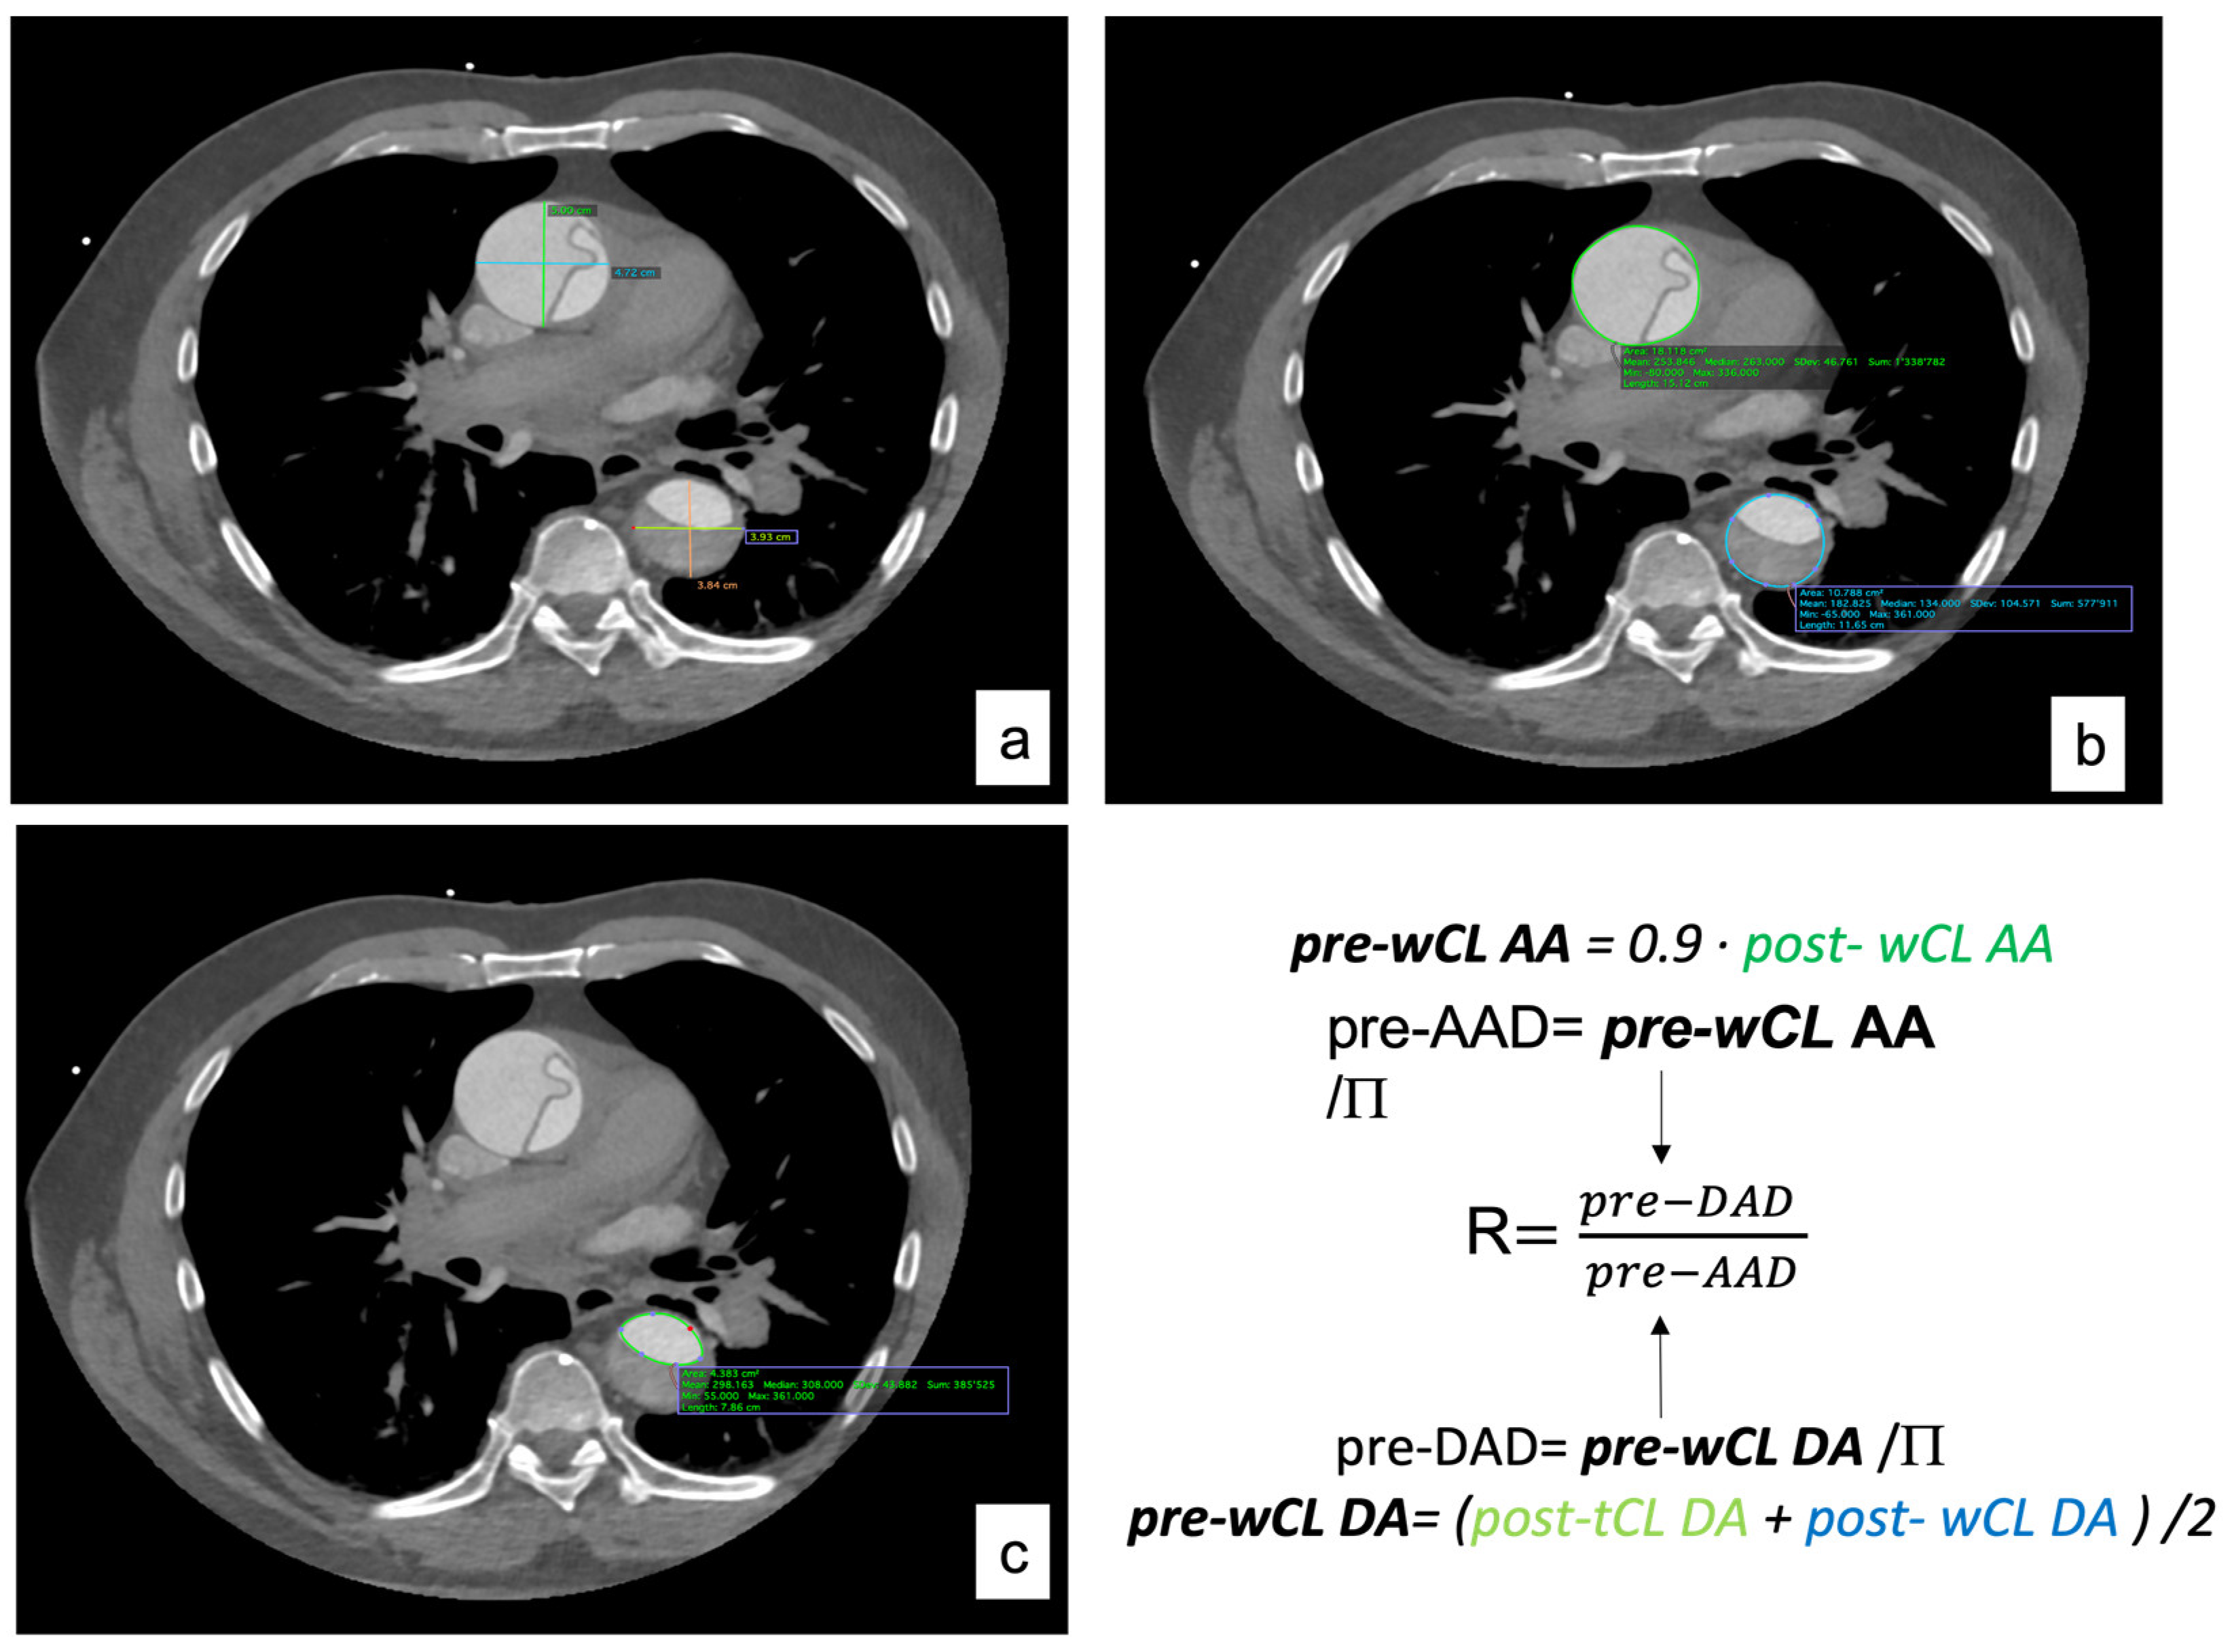

2.3. Imagining Analysis